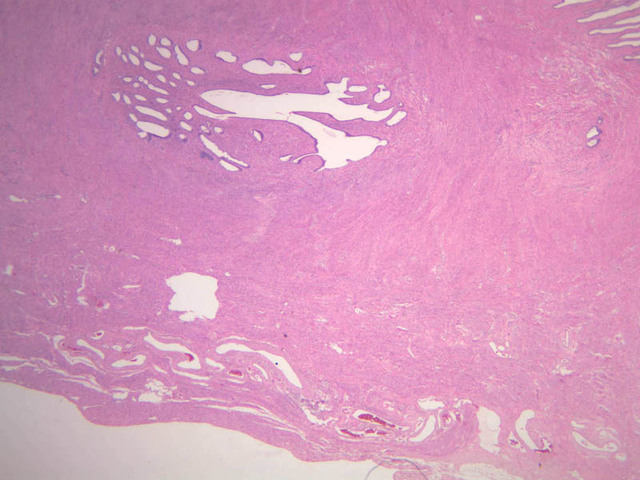

The uterus is a pear-shaped muscular organ, somewhat flattened from front to back. The expanded upper portion is referred to as the fundus, while its lower part, which protrudes into the vagina, is called the cervix. The lumen of the uterus is slit-like and is in communication with that of the uterine tubes (B-97, monkey uterus [1x, 1x, 1x, 1x]). The wall of the uterus consists of three layers: perimetrium, myometrium, and endometrium (B-97 [1x, 1x-labeled] [1x, 1x, 1x]; B-100 [1x, 1x]). The perimetrium is peritoneum which covers the uterus, but is lacking in the posterocaudal third below the peritoneal reflection (B-97 [2.5x, 10x, 20x, 40x]). The myometrium is the very thick middle layer consisting of bundles of smooth muscle cells arranged into several interwoven layers (slide B-93 [1x-labeled, 2.5x] [1x, 2.5x] [1x, 2.5x] [2.5x, 10x, 20x, 40x]). The endometrium is the innermost layer and is a glandular mucosa (B-97 [2.5x, 10x, 20x] [2.5x, 10x, 20x] [2.5x, 10x, 20x, 40x]). It consists of a surface epithelium which is invaginated into tubes called uterine glands. The glands penetrate into a very thick lamina propria referred to as the endometrial stroma. The surface epithelium is a mixture of ciliated and non-ciliated simple columnar cells, whereas the glandular epithelium consists mainly of non-ciliated secretory cells. The endometrial stroma has the appearance of a loose, rather cellular mesenchyme with numerous blood vessels.

The endometrium is subdivided into two main parts; the basalis and the functionalis (slide B-97). The basalis is deep, lying adjacent to the myometrium, it consists of stroma and the closed ends of the uterine glands and is not sloughed during menstruation. The functionalis is upper zone consisting of the remainder of the uterine glands with intervening stroma. It is lost during menstruation, but is replaced again with each menstrual cycle, by proliferation of the persisting elements in the basalis.

The menstrual cycle is a continuous series of events, dominated by the endocrine activity of the ovary, which repeats itself with a 28 day period. The endometrium participates by undergoing a series of structural changes which are roughly divided into three categories, the proliferative, secretory, and menstrual phases. These phases are listed below, examine each of the uterine slides and determine to which phase it belongs.

Proliferative Phase

This phase occurs during days 7 to 14 and corresponds to the ovarian follicular phase with rising levels of estrogens. The functionalis layer is replaced by growth of the endometrial elements in the basalis. The glands are usually straight tubes extending from the surface. Epithelial cells become taller and accumulate glycogen basal to their nuclei. (slide B-93 [2.5x, 10x, 20x, 40x]; B-97 [2.5x, 10x, 20x, 40x])